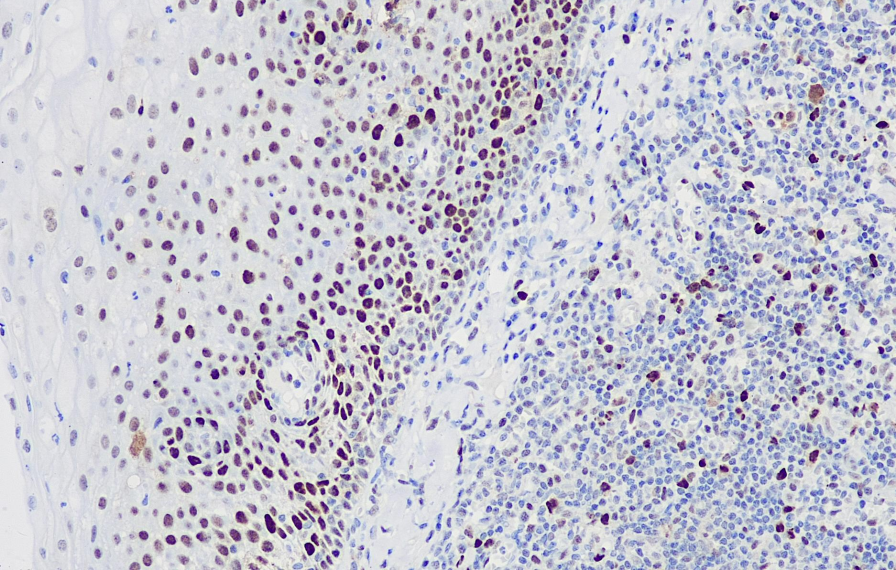

Cellular localization: nucleus

Positive control: tonsils

PCNA is a 36kD nucleoprotein related to the cell cycle and is an essential protein for DNA synthesis in cells. This antibody can be used as the main reference basis for cell proliferation index, for studying the cell proliferation of malignant tumors and judging their malignancy degree, which has certain significance for the treatment and prognosis research of tumors.

PCNA antibody reagents can specifically bind to PCNA molecular antigens. Immunohistochemical kits containing PCNA antibody reagents are suitable for evaluating the proliferation activity of tumor cells (such as lymphoma, glioma, and digestive tract cancer).